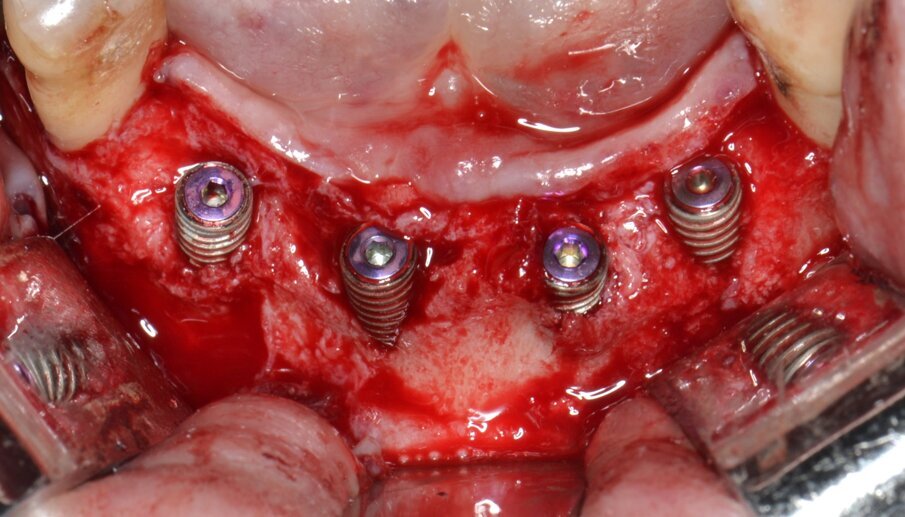

Sulla scorta dei dati ottenuti dalla simulazione effettuata con software Real Guide Ver. 5.0 (3Diemme, Como) si procede all’inserimento di quattro impianti endossei misura 3,5x13 mm. Resista IA3413 (Resista, Via F.lli Di Dio, 68 – Omegna, VCO) allo scopo di ottimizzare la stabilità primaria nel tessuto osseo residuo: come previsto dalla pianificazione pre-chirurgica, un’ampia porzione di superficie implantare rimane esposta (Figg. 6, 7). Due membrane di tipo non riassorbibile in PTFE misura 25x30 mm. MED2530 Medipac (Resista, Via F.lli Di Dio, 68 – Omegna, VCO) vengono allocate sull’aspetto orale della cresta atrofica e fissate saldamente alla corticale linguale mediante viti da osteosintesi autoperforanti VOS da 6 mm di lunghezza (Resista, Via F.lli Di Dio, 68 – Omegna, VCO) (Fig. 8).

Fig. 7 - Inserimento di 4 impianti endossei: una consistente porzione della superficie attiva rimane esposta.